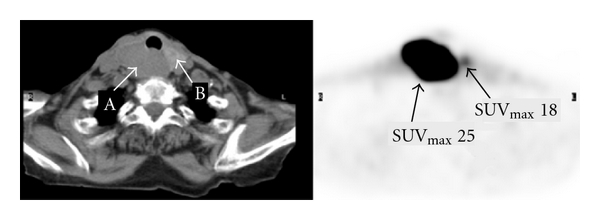

Figures 1–3 represent selected axial images of the PET-CT from 3 case examples, which all demonstrate overestimations of of the lesions directly neighboring large hot sources. In Figure 1, of the myocardium is 7.0, and measured of a 2.0 cm lingular nodule is 5.6 even though there is no visible uptake. Repeating FDG PET-CT six months later in the same patient shows the unchanged, non-FDG avid lingular nodule, but measured is 2.2 due to less intense cardiac uptake ( 4.0) compared to the first scan (the images not shown). In Figure 2, there is no abnormal uptake in the endocervix in the patient with history of cervical cancer and after chemoradiation, but measured cervical is 12. The bladder urine is 20. The subsequent Pap smear was negative for recurrence of cervical cancer. In Figure 3, there is a large, highly FDG avid right-sided thyroid lesion with 25. A 1.5 cm nodule in the left lobe of the thyroid demonstrates much less uptake than the right, but measured is 18. In all of the three examples above, the SUVs of the lesions (lung nodule, endocervix, and left thyroid nodule) were unexpectedly overestimated due to their locations in close proximity to the large sources of high radioactivity in the myocardium, urinary bladder and right thyroid mass.